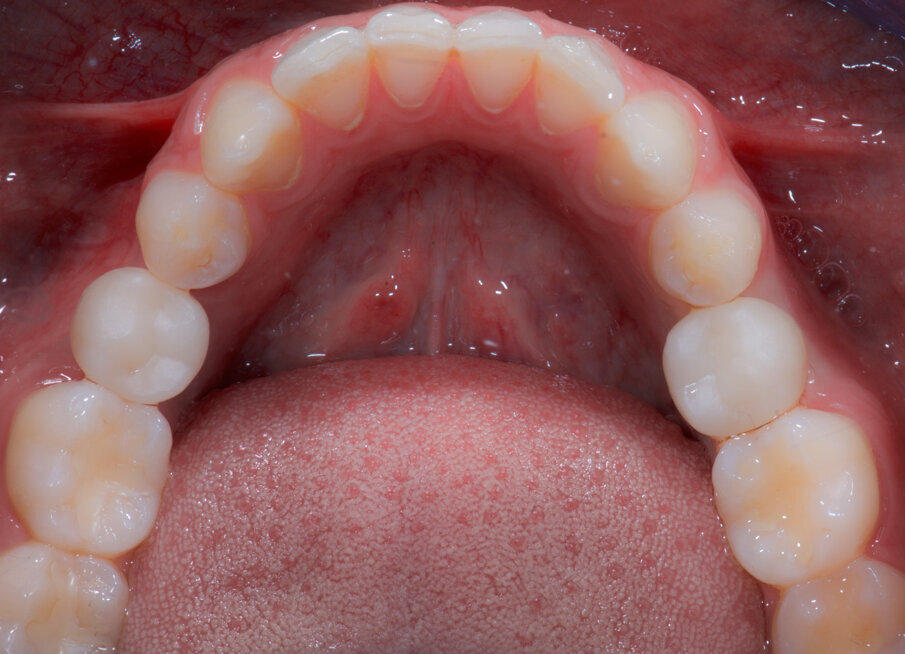

Fig. 1_In evidenza la persistenza dei decidui in quadrante 3-4.

Fig. 4_L’arcata inferiore.